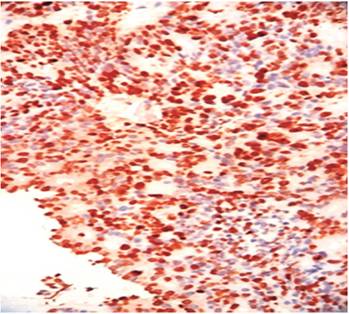

Colonoscopy revealed a rounded 4 cm tumor-like lesion of the same color as the surrounding mucosa at the ileocecal valve. The sign of the tent, elevation of the intestinal wall with a broad base and a blunt apex, could be seen without a pedicle and with the mucosa intact (Figures 3 and 4). A biopsy taken for histological study contained poorly differentiated neuroendocrine carcinoma grade III. Immunohistochemistry was positive for neuron specific enolase (NSE), synaptophysin and Ki 67 (Figures 5, 6 and 7).

Figure 5 Microphotograph of the intestinal lesion showing well-defined nests of malignant tumor cells with neuroendocrine histological features. H/E-20 X.